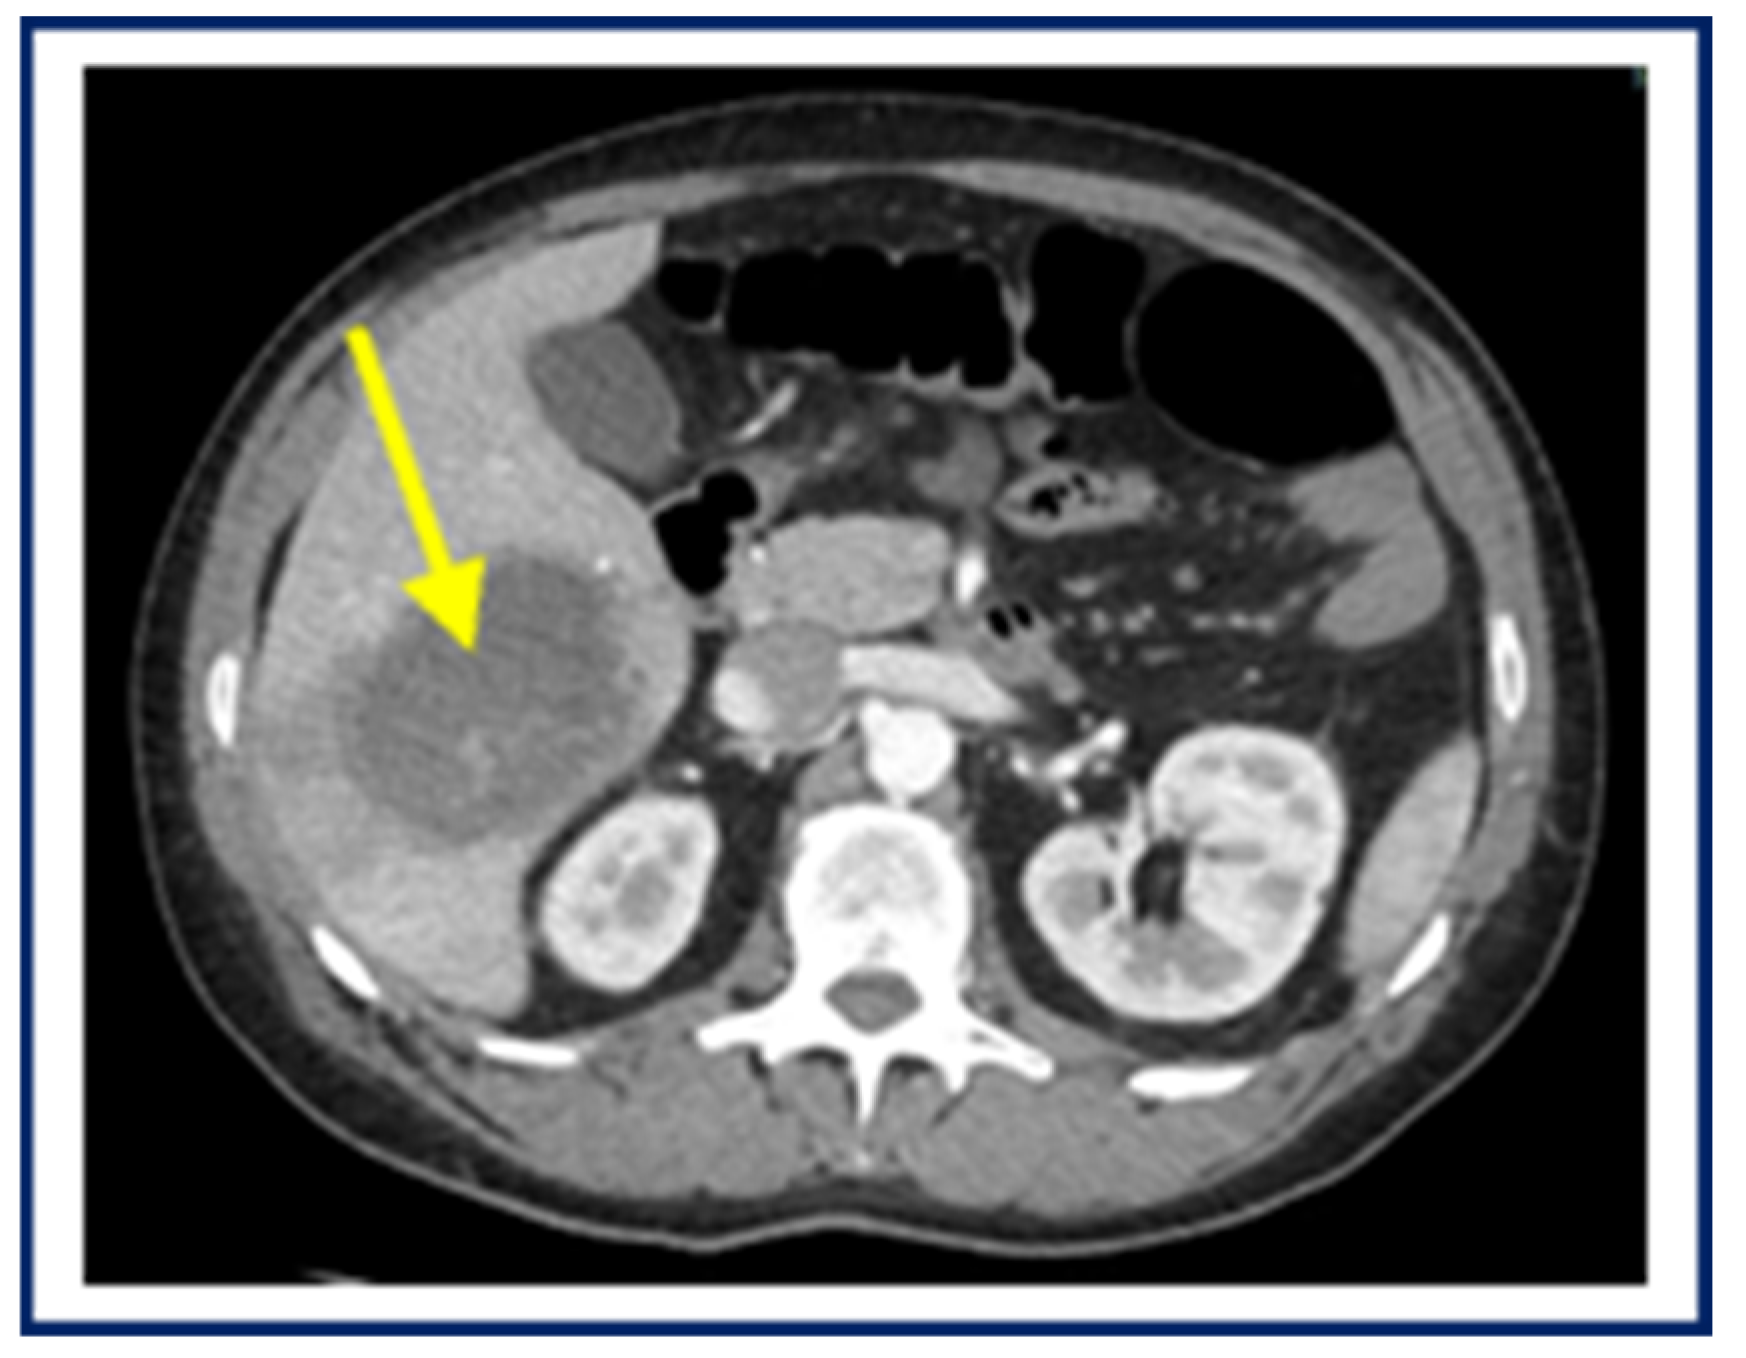

4. Case Report 3